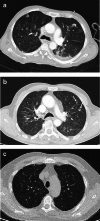

Objectives: Pulmonary Langerhans cell histiocytosis (PLCH) is a rare interstitial granulomatous disease that usually affects young adults who are smokers. Chest computed tomography (CT) allows a confident diagnosis of PLCH only in typical presentation, when nodules, cavitated nodules and cysts coexist and predominate in the upper and middle lungs.

Methods: This article includes a pictorial essay of typical and atypical presentations of PLCH at initial chest CT. Various appearances of PLCH are illustrated and possible differential diagnosis is discussed.

Results: PLCH can present with some aspecific features that may cause diagnosis of the initial disease to be overlooked or other pulmonary diseases to be suspected. In cases of nodule presentation alone, the main differential diagnosis should include lung metastasis, tuberculosis and other infections, sarcoidosis, silicosis and Wegener's disease. In cases of cysts alone, the most common diseases to be differentiated are centrilobular emphysema and lymphangiomyomatosis. Clinical symptoms are usually non-specific, although a history of cigarette smoking, coupled with the presence of typical or suggestive findings at imaging, is key to suspecting the disease. Atypical presentations require surgical biopsy for diagnosis.